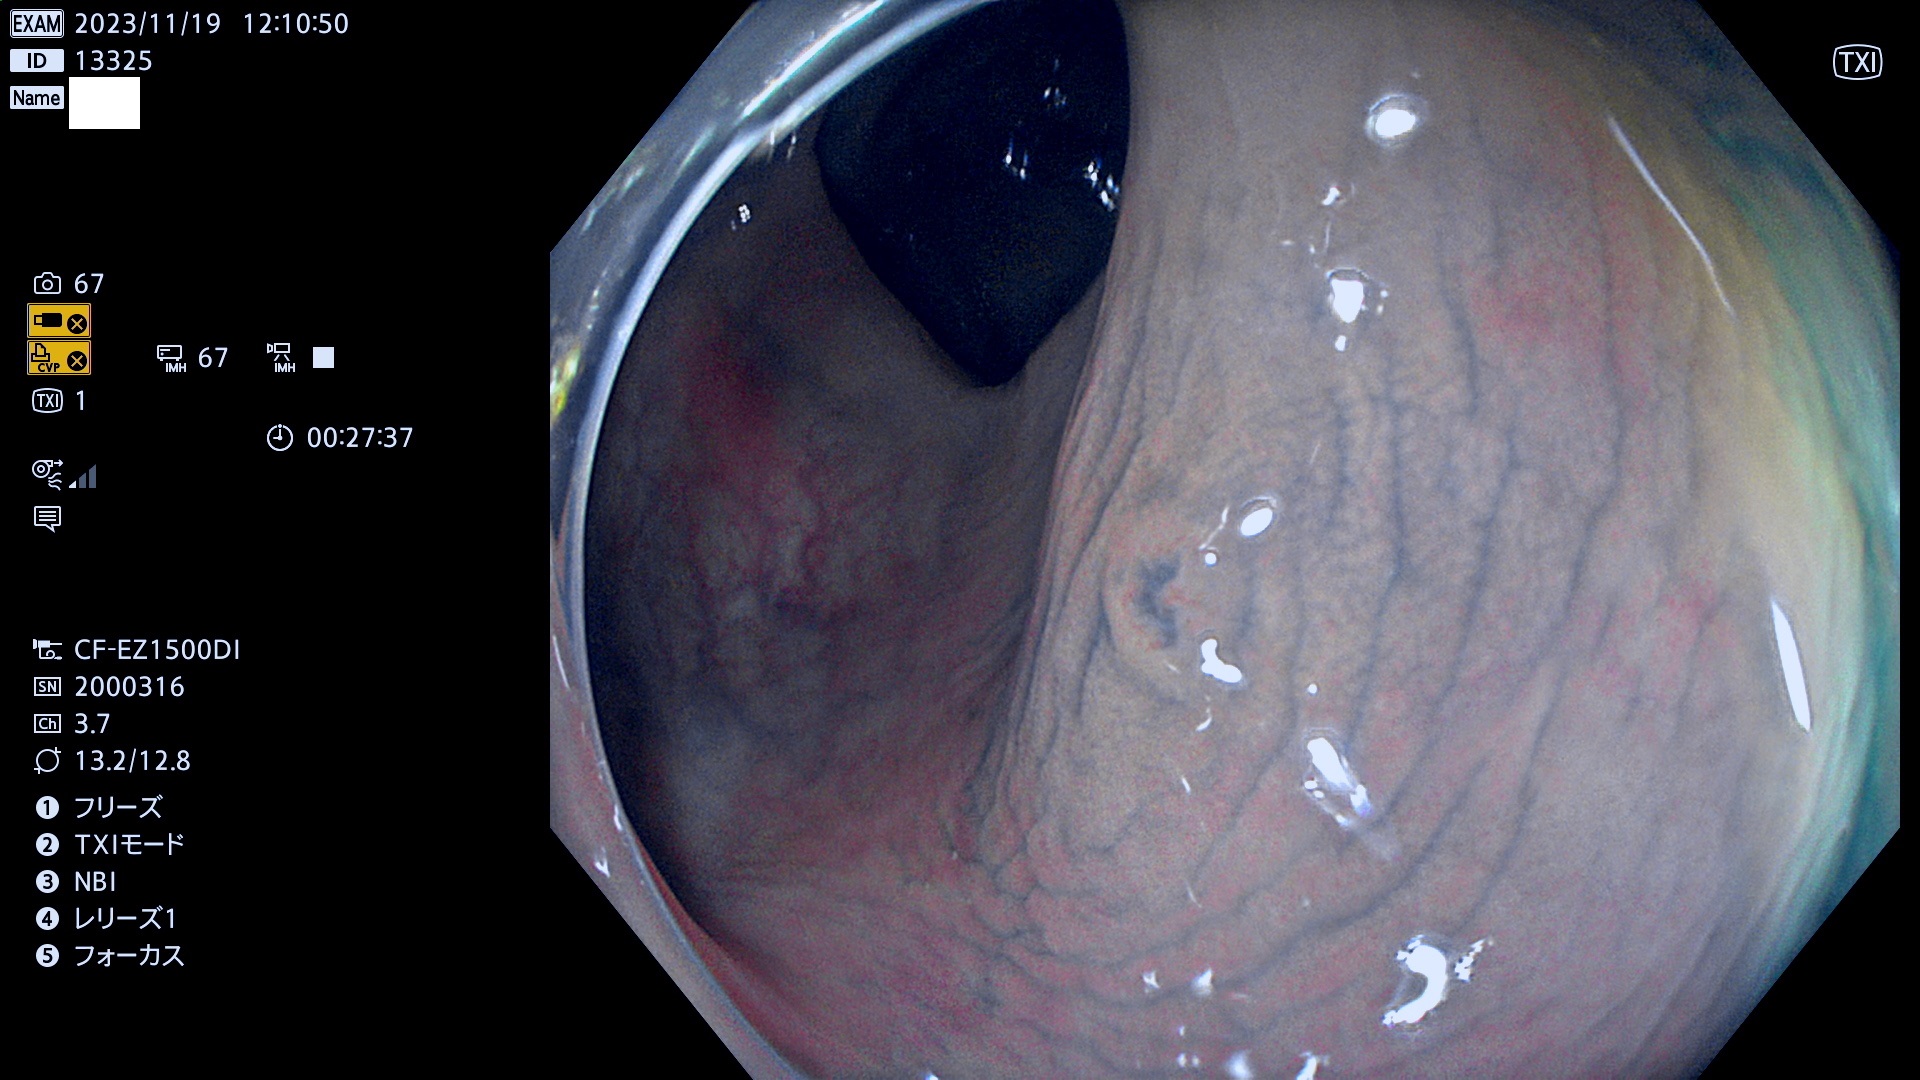

今週のUb、Uc型腺腫

表面型腺腫(Flat Adenoma)の中で、完全に平坦な物をUb、陥凹している物をUcと呼びます。平坦隆起型(Ua)よりも、発見が難しく危険な病変です。このタイプは「内視鏡後・大腸癌の重要犯人」であり、この発見率は「腺腫発見率」よりも、重要な意味があります。

毎週の検査(木・金・土・日)に発見されたUb、Uc型・腺腫を、その週の日曜の夜にUPし1週間、提示します。

抽出の対象期間 2023年11月16日(木)〜11月20(日)の5日間(60件の検査)11件